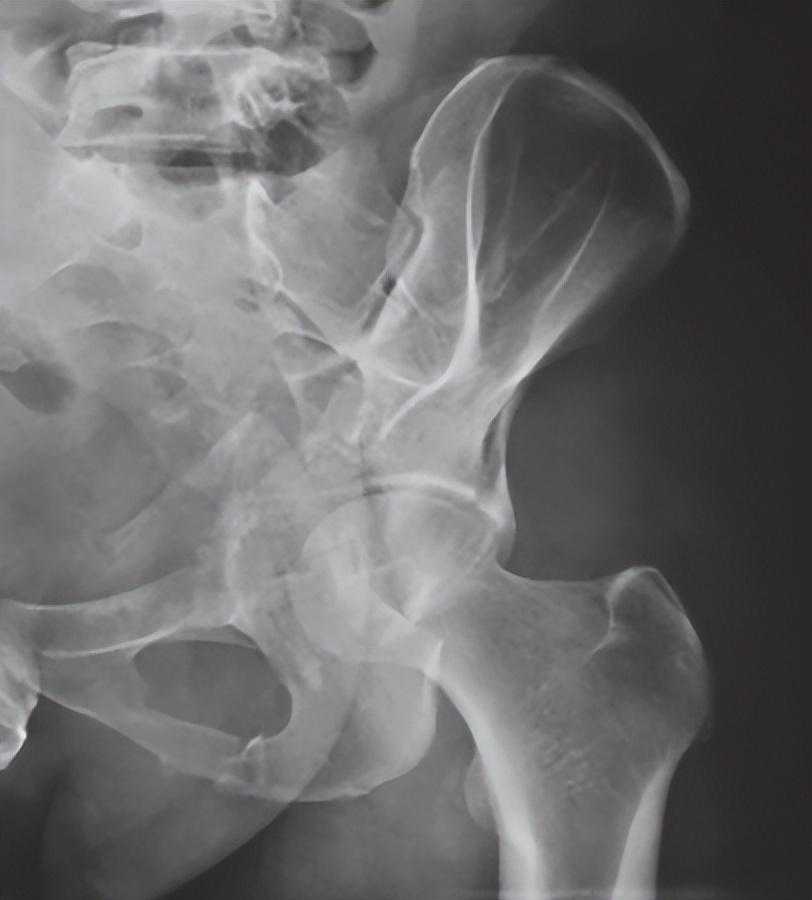

2、骨盆入口位X线检查:

可显示骶骨、髂骨后上部、骶髂关节上方、耻骨联合、耻骨支上缘及髋臼顶弓等。可用于鉴别骨盆环骨折的前后移位、旋转畸形、耻骨联合分离等(图2-3)。

图2骨盆入口位X线片1,可见左侧髂骨体骨质破裂,部分骨块分离,累及髂骨翼及骶髂关节面;左侧耻骨上、下支骨折,累及耻骨联合,提示骨盆前环损伤;双侧骶髂关节对位可,并未发生前后旋转移位